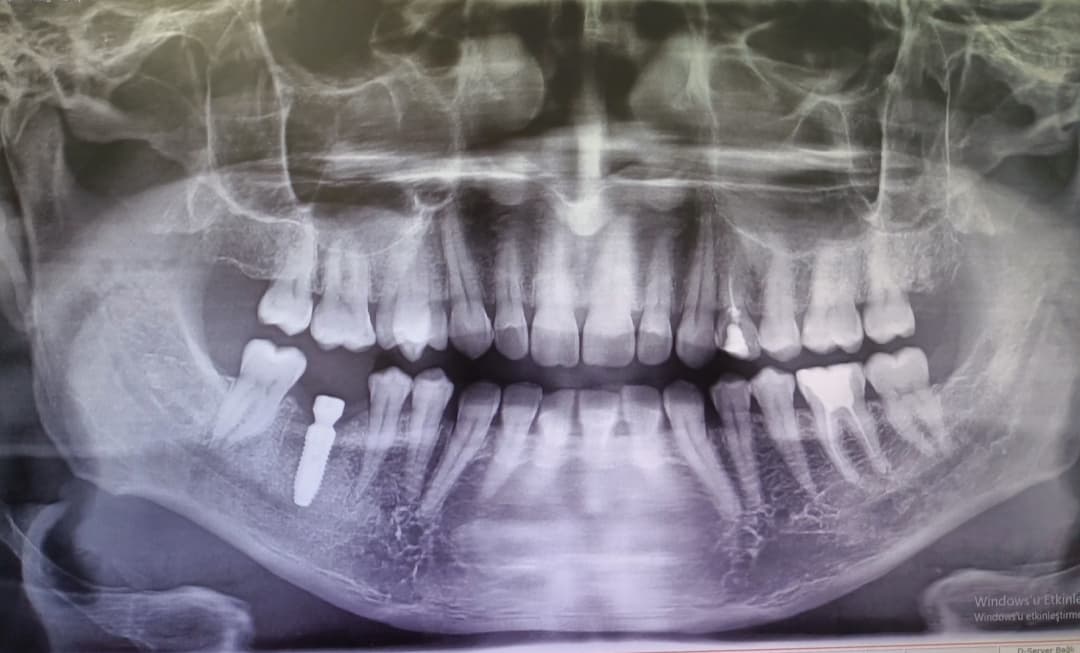

I came to istanbul for a short trip from London. I have done my treatment with Dr Gokhan at Seba Dis Clinic. His work is highly recommended. Professional and polite. He made sure that I will get the best result of the whitening treatment. He’s very good at his work. I am happy with the result as my teeth whitens 5-6x shades with visible results after the treatment. The whole team was very helpful on our visit. They’re also friendly and accomodative. Had the chance to meet Dr Mert and he’s also exeptional. I booked my consultation with him, he also explained that he’s a specialist for medical and gave professional advise on our xray. Will come back again to them for any teeth procedures. Five star⭐️⭐️ ⭐️ ⭐️ ⭐️